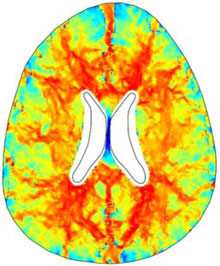

A numerical finite element model of one human brain is built in COMSOL in order to study a particular form of hydrocephalus, the so called Normal Pressure Hydrocephalus (NPH). The geometry of the ventricles and the skull is obtained by Magnetic Resonance Imaging (MRI) and imported in ... 詳細を見る